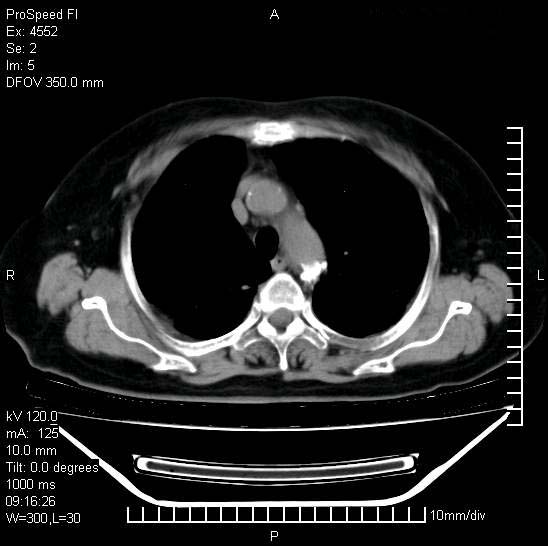

标题: CT15528:女性,79岁,近几日晚上高热,39度,仍咳少量血 [打印本页]

十几年前曾患肺结核,一周前突咳血约100ml,中性粒细胞稍高,诊断两上肺陈旧结核,下肺炎症,给予抗炎治疗,近几日晚上高热,39度,仍咳少量血,4天前ct及今天ct上传。

今天ct

短短几天内,病变范围明显增多扩大,以左侧明显,而且双侧出现胸水,还是考虑感染.

无论是肿瘤还是炎症4天的时间都发展够快的,并且还在治疗中,如果说是左肺癌那么右肺的病变不好解释,本人更加倾向于炎症,左肺舌叶支气管被痰栓或血凝块堵塞,造成阻塞性肺炎。

陈旧性肺结核及左下肺不张,咯血后肺部感染,双胸腔积液,高热可能与痰液引流不畅有关。